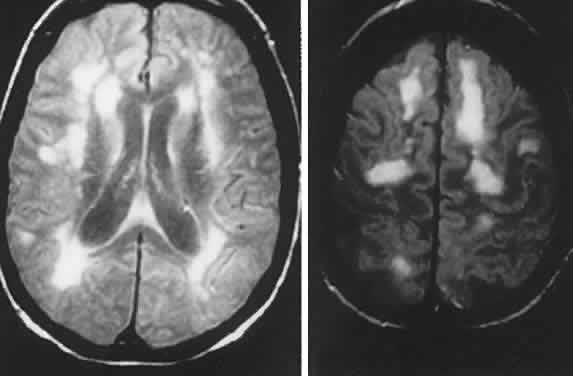

Other subsets of pigmentary retinopathies are due to mitochondrial DNA mutations and are associated with migraine, ataxia, dementia, and Leigh's disease17; the sporadic or maternally inherited MELAS syndrome of mitochondrial myopathy, encephalopathy, lactic acidosis, and stroke-like episodes, usually presents in the teens as cognitive regression, headaches, and cerebral lesions causing field defects.18–20 Even in family members, there is considerable variation of genotypic and phenotypic specificity in metabolic disorders mediated by mitochondrial DNA aberrations, including Kearns-Sayre progressive external ophthalmoplegia (see Volume 2, Chapter 12) and other conglomerations of pigmentary retinopathies. Further identification of gene point mutations will eventually provide a more precise classification.

As noted above, Gass1 and others have elaborated a class of acute and subacute, diffuse or focal, presumed inflammatory zonal disorders of the outer retinal layers, now termed AZOOR. Roughly described as “enlarged blind spots” and thus confounding neurologic diagnosis, this somewhat heterogeneous rubric includes MEWDS (multiple evanescent white dot syndrome), multifocal choroiditis, acute macular neuroretinopathy, pseudo-presumed histoplasmosis, and idiopathic blind spot enlargement. These entities share a constellation of signs and symptoms and so raise the question of a spectrum of common origin involving geographic zones of retinal photoreceptors and pigment epithelium. Characteristics include the following: predilection for female patients; acute onset in one or both eyes, associated with photopsias; minimal fundus findings at onset, but eventual minor pigment epithelial disturbances; ERG abnormalities; fluorescein angiographic evidence of geographic thinned pigment epithelium; vitreous cells; and permanent field depressions often close to the physiologic blind spot. Taken as a group, Jacobson and colleagues2 investigated the nature of retinal dysfunction and found patchy but dense scotomas and ERG abnormalities, but no evidence of autoantibodies to specific retinal antigens. Recurrent central nervous system (CNS) inflammation in association with AZOOR is reported,23 characterized by cerebrospinal fluid (CSF) lymphocytosis and multiple magnetic resonance imaging (MRI) signal abnormalities, followed in 6 years by an episode of cervical myelopathy.